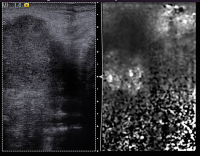

Lymphknoten-Ultraschall

Abbildung 5: Ultraschallkontrastmittel. Das Ultraschallkontrastmittel verbleibt als rein gefäßgängiges Kontrastmittel nur in den Blutfgefäßen und tritt nicht in das Parenchym über. Das Signal stellt somit ausschließlich das Kapillarnetz sowie die zu- und abführenden Gefäße dar. Normalbefund.

Abbildung 6: Ein bereits nativ suspekter Lymphknoten (zervikale Adenokarzinommetastase von der Lunge) zeigt im Power-Doppler kaum ein Gefäßsignal, nach Kontrastmittelapplikation ein heterogenes Enhancement, v.a. mit einzelnen Kontrastmittelaussparungen.